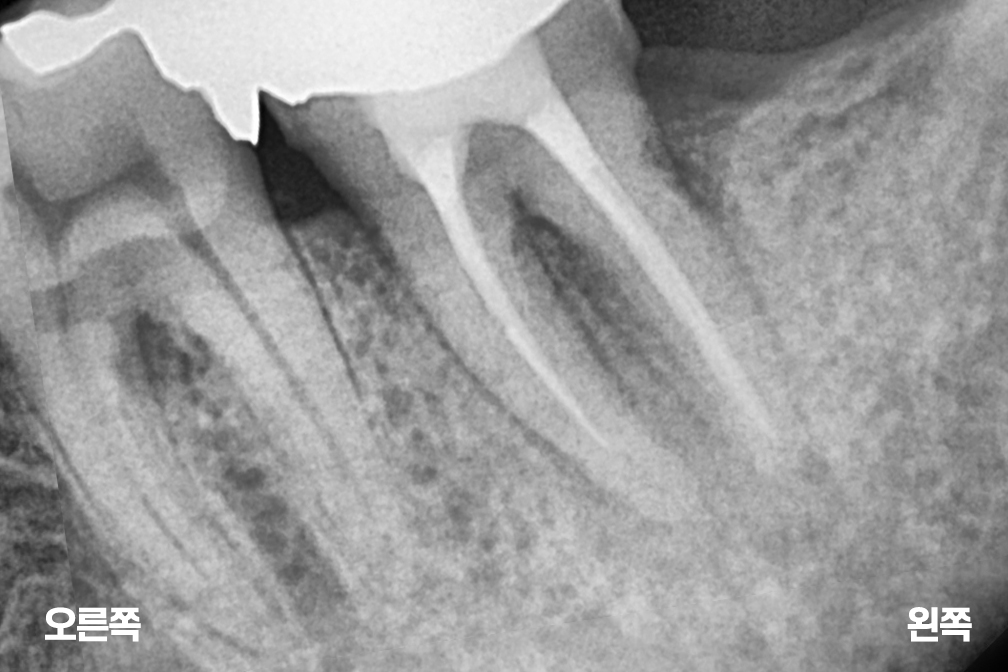

재신경치료

After 2026년 1월 20일